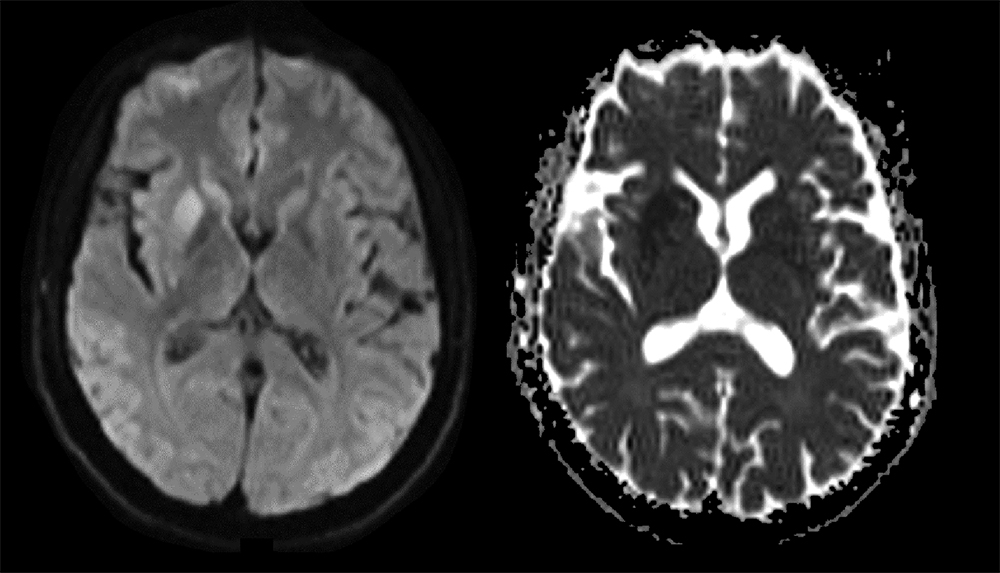

Creutzfeldt-Jakob disease typically presents as rapidly progressive dementia. We describe the case of a 59-year-old male patient presenting with sudden onset of centra...

read article